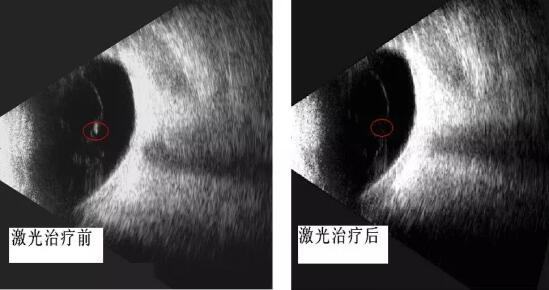

成人导航 眼科开启"灭蚊"时代 ――飞蚊症的治疗